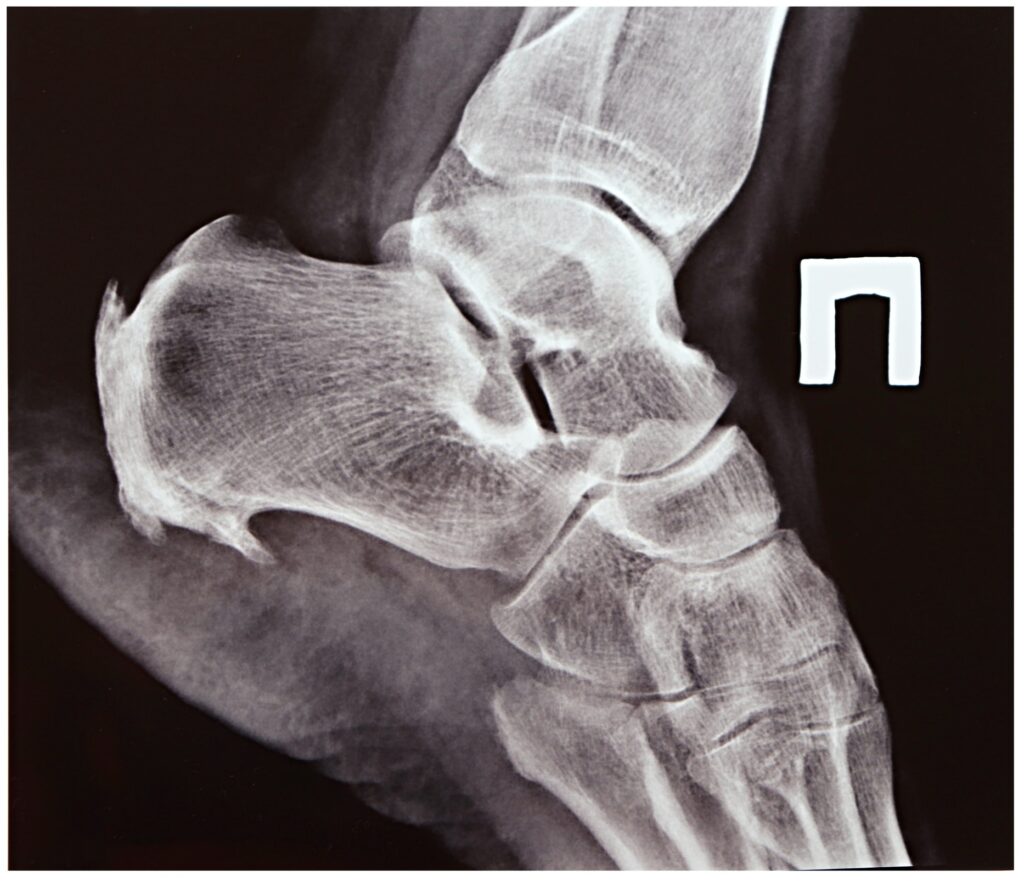

Plantar fasciitis is the inflammation of the plantar fascia, the thick band of tissue that runs across the bottom of your foot, connecting your heel bone to your toes. This condition is a leading cause of heel pain and is particularly common among veterans due to the intense physical activity and stress their feet endured during service.

This painful condition manifests as a sharp, stabbing pain in the bottom of the foot, near the heel. The pain is often most severe with the first steps in the morning or after long periods of rest. For veterans, this isn’t just a minor annoyance; it’s a chronic issue that can severely impact mobility and quality of life. The daily duties of military life—such as rucking with heavy gear, running on uneven terrain, and prolonged standing—are significant contributing factors. These activities can cause repetitive strain and micro-tears in the plantar fascia, leading to inflammation and chronic pain that persists long after service has ended.